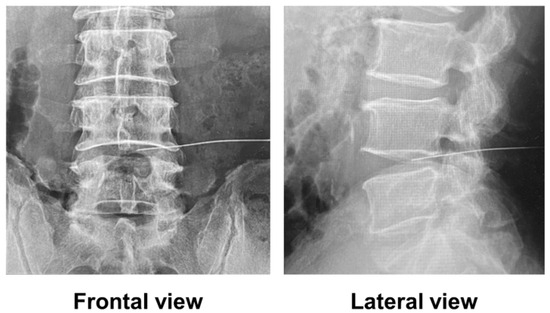

The mean intervertebral disc height significantly decreased from 8.4 mm before treatment to 6.9 mm after treatment (95% CI, 0.990–1.877; p < 0.001). MRI evaluation showed that five of the six patients had T2 high signal intensity in the herniated disc before treatment. Recurrent disc herniation types were protrusion in two patients and subligamentous extrusion in four patients. All herniated discs were located laterally in the spinal canal and compressed nerve roots. There were no massive herniated discs compressing the cauda equina. Before treatment, the Pfirrmann grades were III in two patients, IV in two patients, and V in two patients. After treatment, the Pfirrmann grade changed from III to IV in one patient. Disc herniation resolved in two patients after condoliase treatment (Figure 4) but persisted in four patients. Of the four patients with residual herniation, two showed a reduction in the size of the herniation, and two showed no change in size. The two patients who showed no change in LDH size required revision surgery at 7 and 12 months post-treatment.

Figure 4.

Representative magnetic resonance images before and 3 months after the treatment of a patient with herniated disc resolved by condoliase treatment. A white arrow indicates a herniated disc.